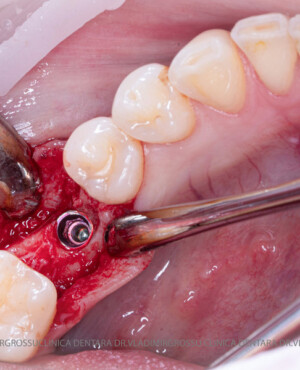

După extracția dentară, în intervalul de 6-12 luni, osul alveolar suferă un proces natural de remodelare, ceea ce conduce la scăderea volumului osos prin rezorbție. De aceea, inserția implantului dentar este ideală imediat după extracție sau, cel târziu, în primele 3-4 luni după aceasta.Scopul procedurilor de adiție osoasă este refacerea fundației osoase necesare pentru stabilizarea corectă a implantului dentar. Pentru ca un implant să reziste în timp la forțele masticatorii, este nevoie de o bază osoasă solidă și sănătoasă.

Procesul de refacere osoasă este complex, însă, simplificat, se bazează pe faptul că osul adăugat se integrează treptat, fiind înlocuit parțial cu os natural, oferind astfel suportul necesar implantului.

Un element esențial în procedura de aditie osoasă este utilizarea membranelor biologice, care izolează materialul osos de țesuturile moi (gingie) pe durata procesului de vindecare. Cele mai recomandate sunt membranele resorbabile din colagen sau pericard.